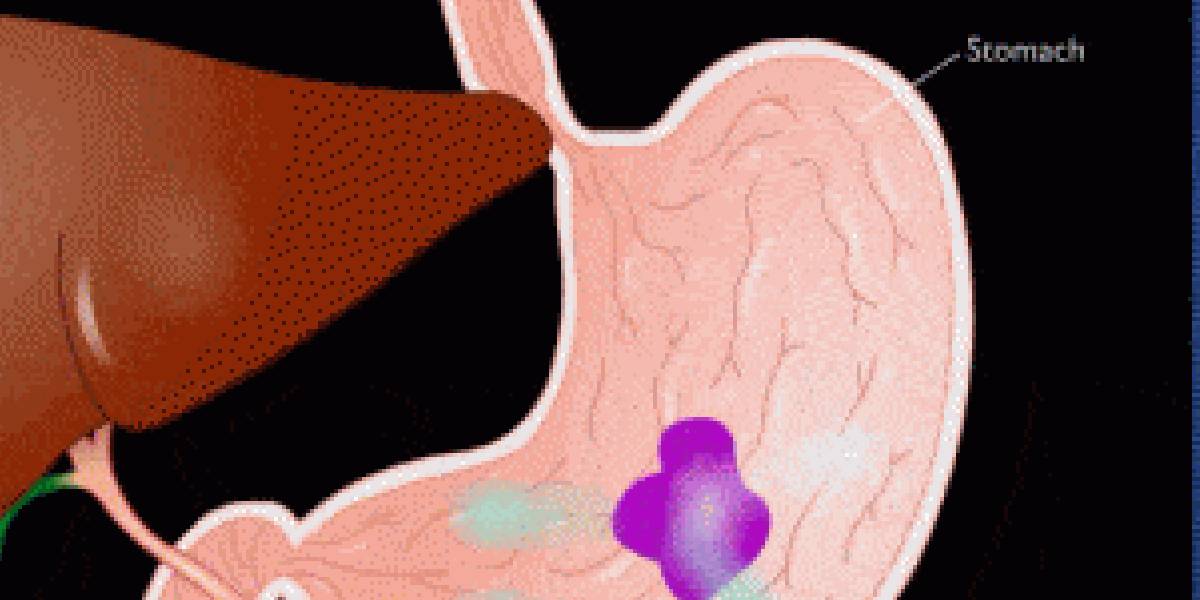

Advanced Technology is transforming healthcare, enabling faster diagnoses, more precise treatments, and improved patient outcomes.

Quality medical equipment ensures accurate diagnoses, effective treatments, and enhances patient safety, contributing to better healthcare outcomes.